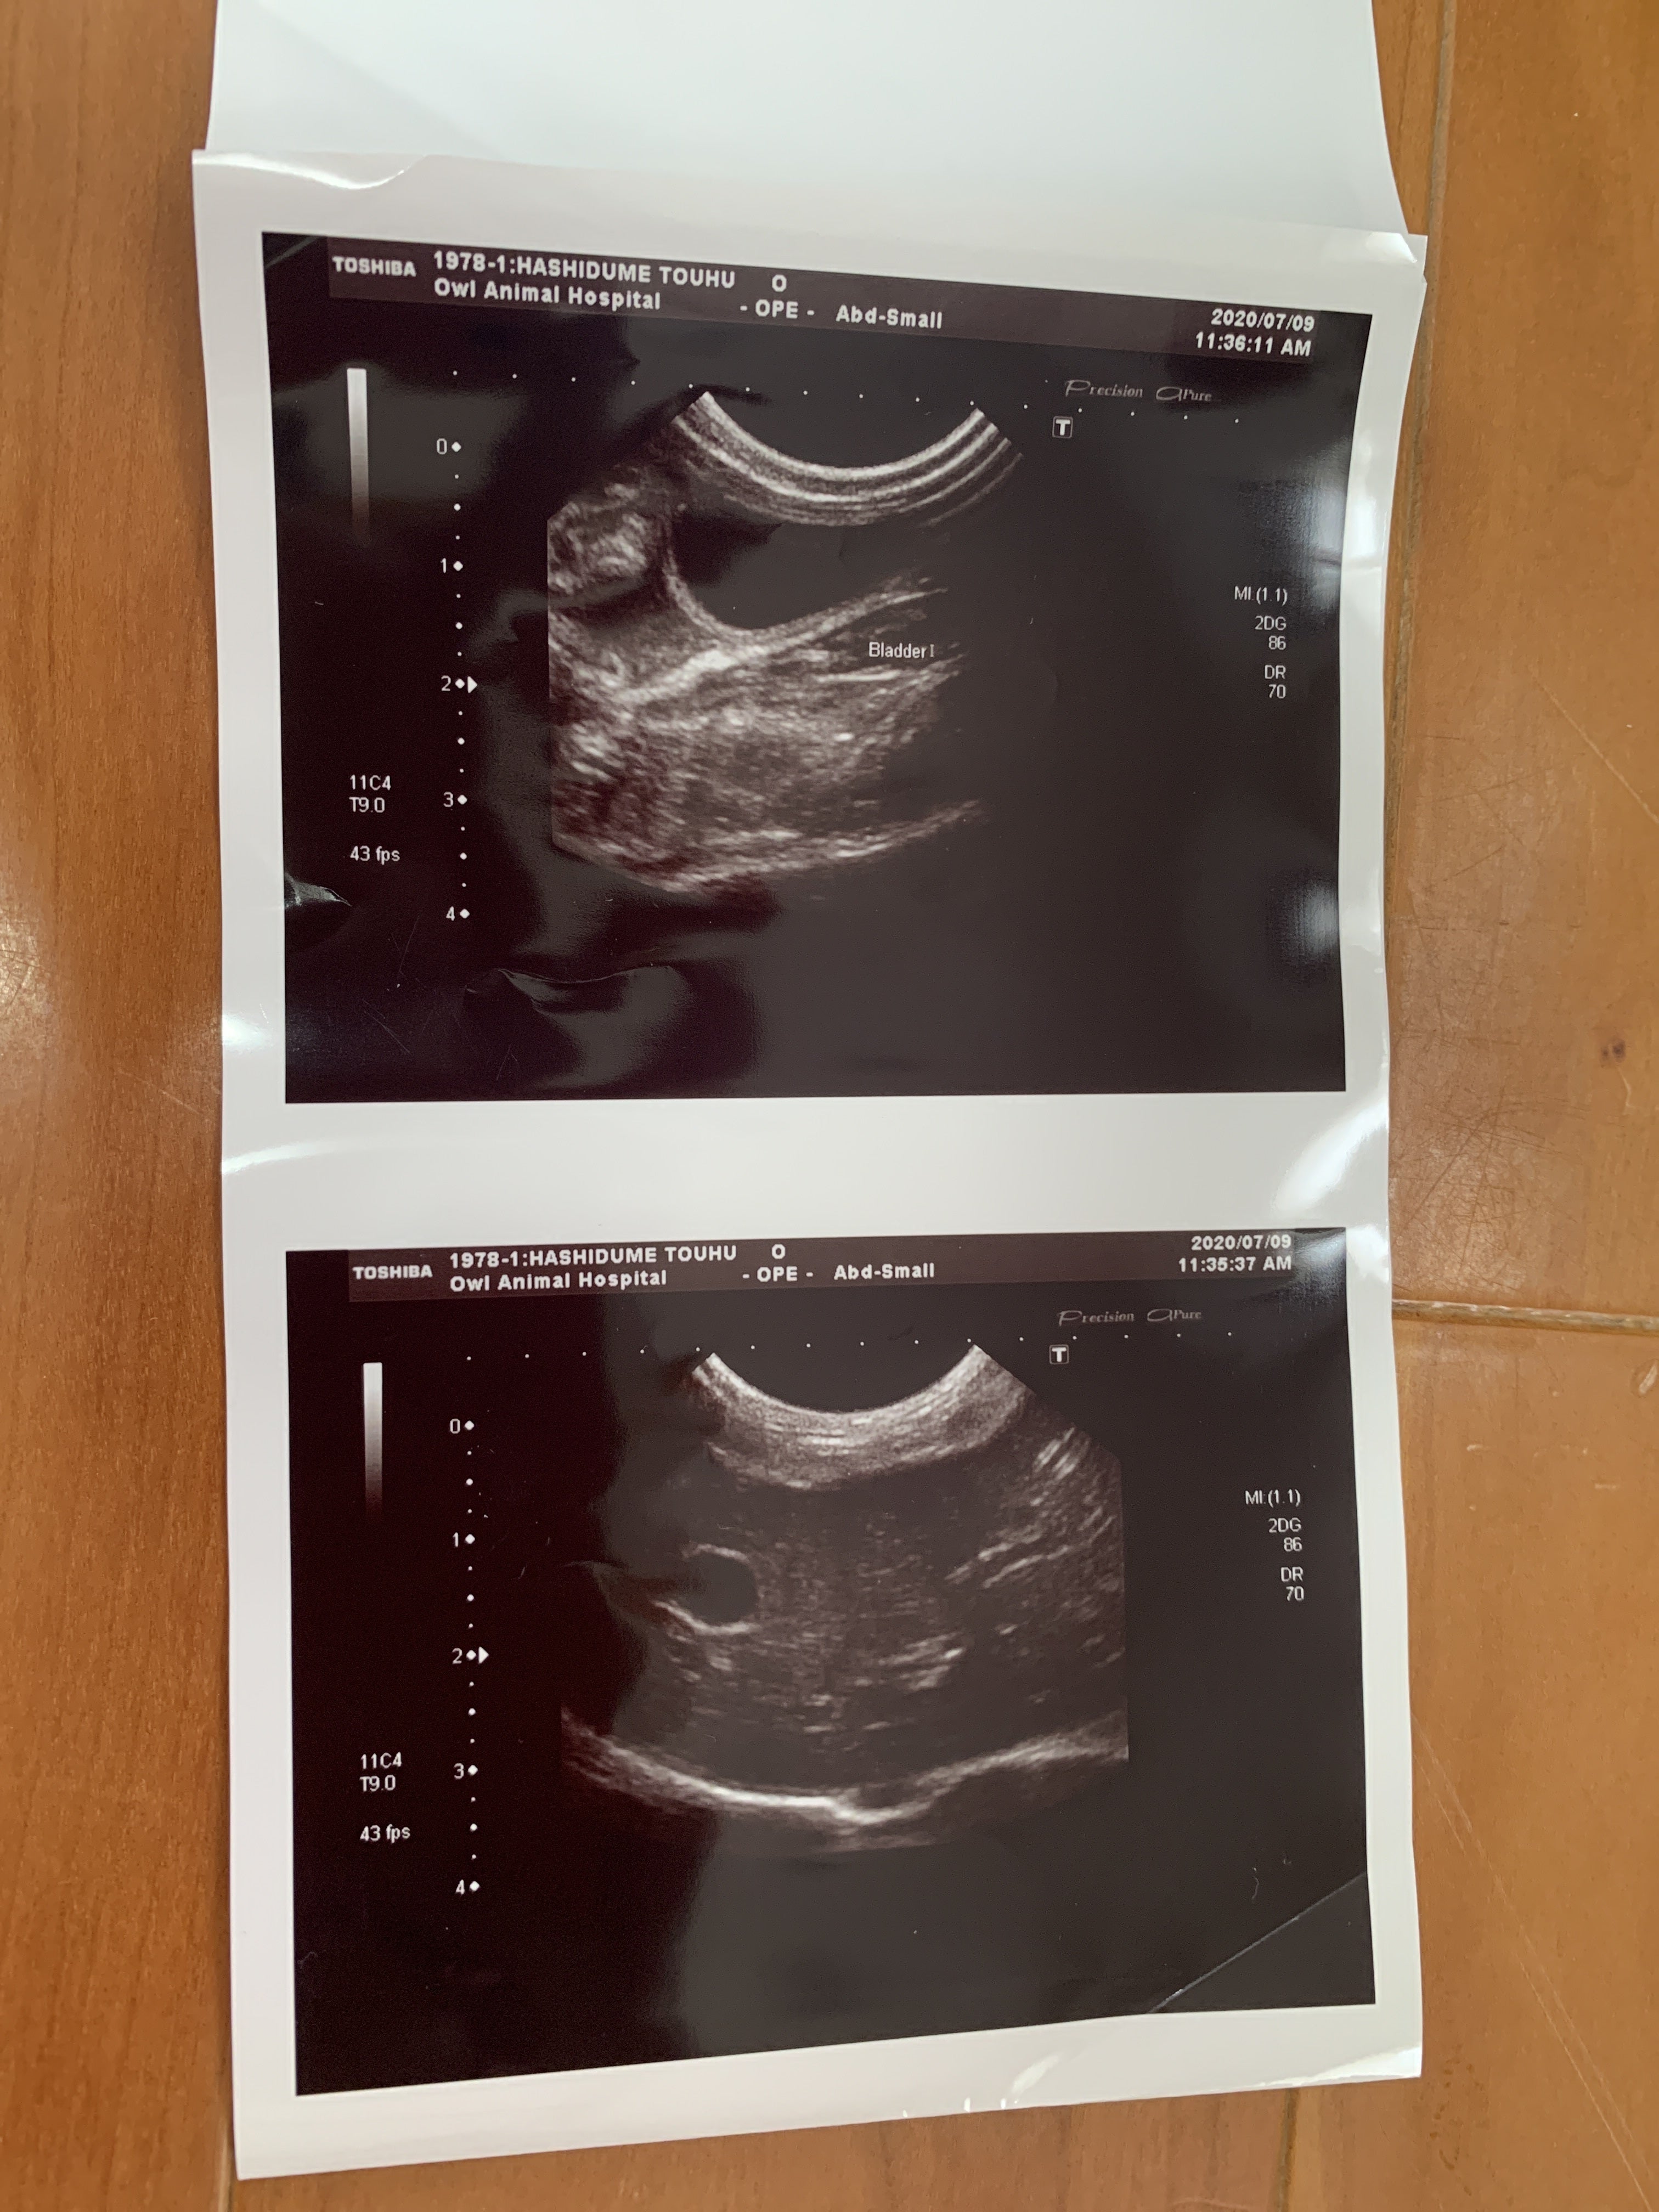

7月9日 朝から病院に連れて行きました。血液検査とエコーの結果

ここで初めて猫伝染性腹膜炎かも知れないと言われました。少しお腹が膨らんでいるのは便秘ではなく腹水でした。私は初めてその病名を聞きました。先生が言うには、このFIP と言う病気は進行が早く数日〜2か月で亡くなる怖い怖い病気ですとの事でした。その後の先生の話を涙が流れるのを必死にこらえて聞いていました。

ウェットタイプは腹水が溜まっていくので、見た目も分かるし、腹水を使った検査でFIP と分かるので診断が早い。

ドライタイプは身体の中で色々な器官に暴走したウイルスが悪さをして、身体の変化が出るまでに時間がかかり、発見がウェットタイプより遅れがちになるそうです。